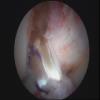

ACL Hamstring graft at insertion